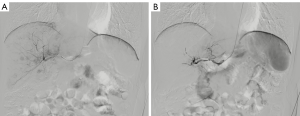

All patients signed informed consent before operation. For patients with a moderate/high preoperative bleeding tendency, preoperative bleeding prevention strategies were performed, including anticoagulant discontinuance before operation, vitamin K injection and/or liver function protection (19). A pre-procedural RA assessment was performed, including the Allen test, as well as an inner diameter inspection by ultrasound. The left RA puncture was performed one centimeter proximal to the styloid process of the radius under local anesthesia (Figure 1A,B). After puncture success, a 4-Fr or 5-Fr Sheath Introducer (Merit Medical, South Jordan, Utah, USA) was exchanged, utilizing the Seldinger technique. After the sheath was introduced, a cocktail solution containing heparin 20–30 mg, nitroglycerin 0.1 mg and lidocaine 20 mg was given through the sheath to prevent RA spasm (Figure 1C). Heparin was decreased or not administered in patients with moderate or high bleeding risk (INR ≥1.5), as regulated by the consensus guideline of SIR and Cardiovascular and Interventional Radiology Society of Europe (SIR/CIRSE) (19). Then, a 125 cm, 4-Fr MPA catheter was inserted through the sheath to the aorta over a hydrophilic guide wire. The catheter was used to cannulate the celiac trunk, hepatic artery, superior mesenteric arteries or inferior phrenic artery, if needed. After finding the vessels responsible for supplying the tumor, a 2.7-Fr microcatheter (Terumo Corp, Tokyo, Japan) was introduced over a hydrophilic guide wire. Digital subtraction angiography was performed to identify the tumor vascularity and stain prior to the embolization.

The TACE procedures performed did not included drug-eluting bead embolization or radio-embolization by yttrium90 microspheres. After the procedure, the vascular sheath was removed immediately, and hemostasis was performed with a special Band device (Terumo Corp) (Figure 1D). As the band was deflated incrementally and removed six hours after operation, arterial hemostasis and pulse were reconfirmed. Also, prior to discharge and during a follow-up at about 30 days after discharge, repeat evaluations of the access site and radial pulse were conducted. RAO is defined as the absence of a RA pulse after a negative reversed Allen test, or is defined by a visible obstruction observed by ultrasound.